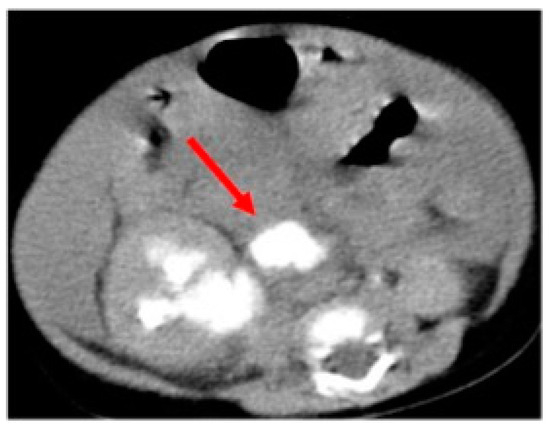

Unfortunately, it was impossible to rise up the JJ ureteral stent to the stenotic PUJ; therefore, a percutaneous nephrostomy was achieved and left in place for one and a half month. Two weeks later, to discern the renal function after the acute hydronephrotic compression and pelvic rupture, he underwent dynamic scintigraphy that showed a symmetric renal function with a right obstructive pattern. To completely understand the anatomy of the right upper urinary tract, a magnetic resonance imaging (MRI) was performed, showing a dysplastic appearance of the PUJ with a coiled junctal ureter and a distal ureter dilatation until the uretero-vesical junction (UVJ) (Figure 3).

Figure 3.

Hydronephrosis on a corkscrew pyeloureteral junction with primary obstructive megaureter at the magnetic resonance imaging.